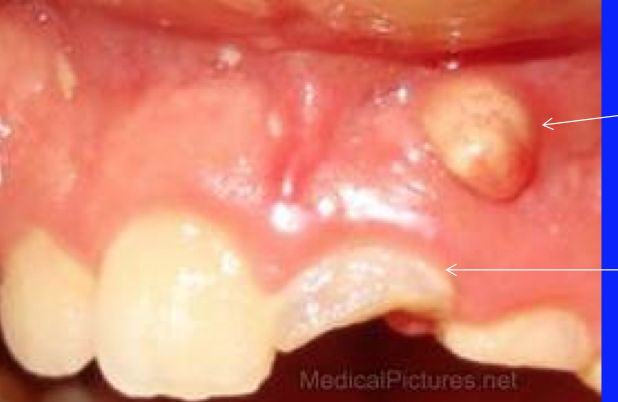

chronic periodontitis

—loosening & separation of teeth